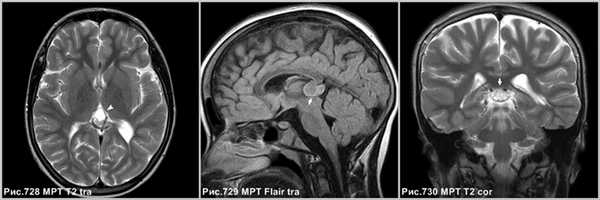

Объёмное образование шишковидной железы, представленное мягкотканным образованием с наличием капсулы (стрелки на рис.729, 730). Пинеоцитома может иметь кисты (головка стрелки на рис.728).

На КТ и МРТ солидные компоненты интенсивно накапливают контраст [34,43,49,53,130].

Интенсивное контрастирование солидных участков пинеоцитомы (стрелки на рис.731-733).